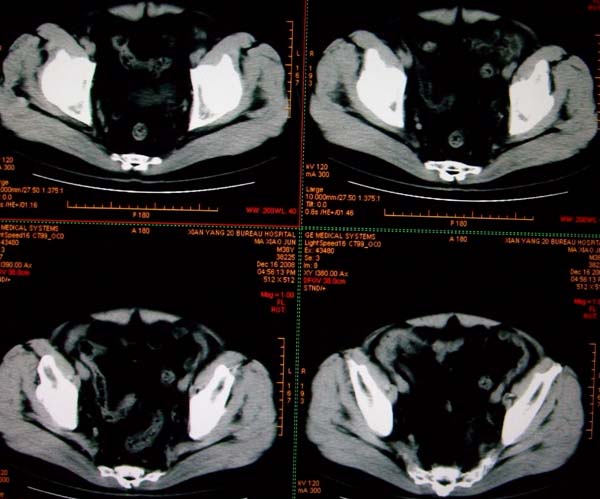

标题: CT17174:M38Y,体检超声提示右肾发育不良,病人无明显不适 [打印本页]

标题: CT17174:M38Y,体检超声提示右肾发育不良,病人无明显不适

右肾发育不良;考虑左肾下极血管平滑肌脂肪瘤可能,建议增强。

右肾微小发育不良  左肾下极错构可能

1)左肾下极占位性病变,不排除肾癌可能;建议行进一步检查。2)右肾发育不良。

左肾下极占位性病变,不排除肾癌可能;建议增强及明确内部组织ct值。右肾发育不良。

右肾发育不良。左肾下极占位。

右肾发育不良。左肾代偿。左肾下极占位,性质待定,建议强化。

右肾发育不良

右肾发育不良。左肾下极占位。建议增强!

右肾发育不良。左肾下极占位。  强化

右肾发育不良。左肾下极囊实性占位,建议增强。